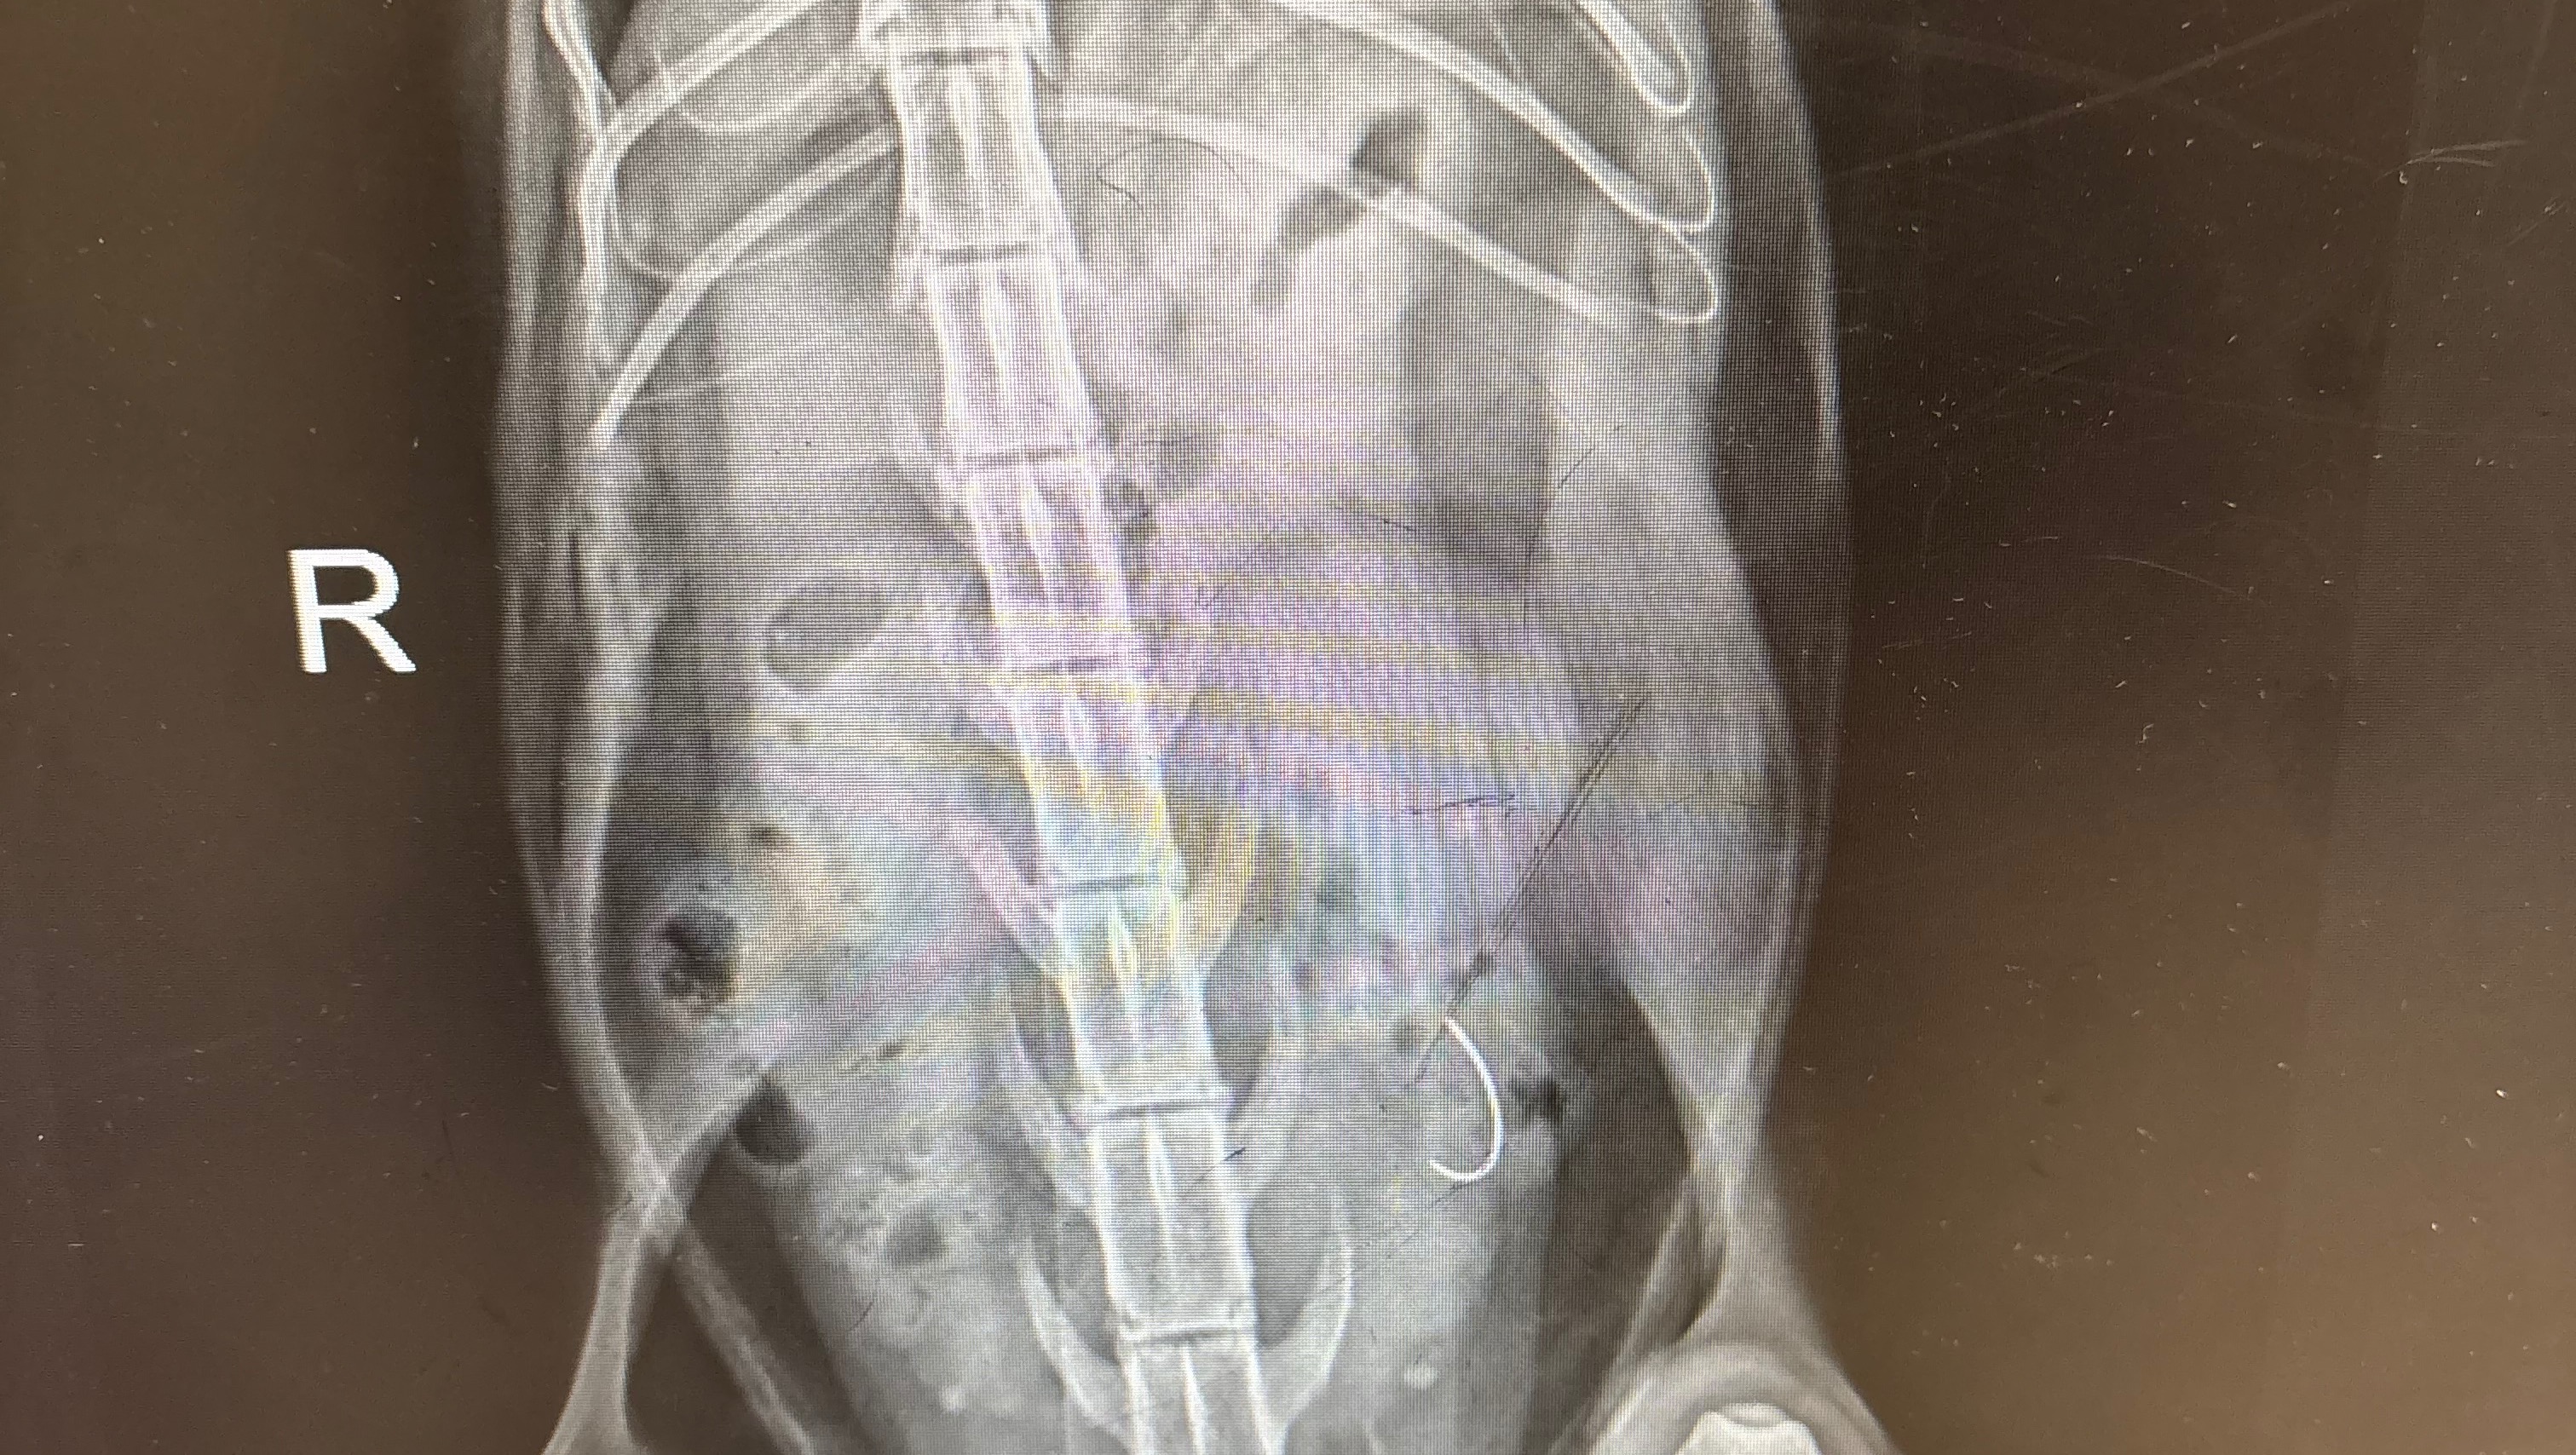

Hi everyone. Noe, Dillon, and I are writing this on behalf of our friend Sam’s cat, Tarzi, who needs to undergo emergency surgery today for the removal of a foreign body (suture needle) she ingested, which is lodged in her small intestine. Tarzi is a beloved 6-year-old cat who has lived with Sam since her early days, and she is now loved by all who have met her.